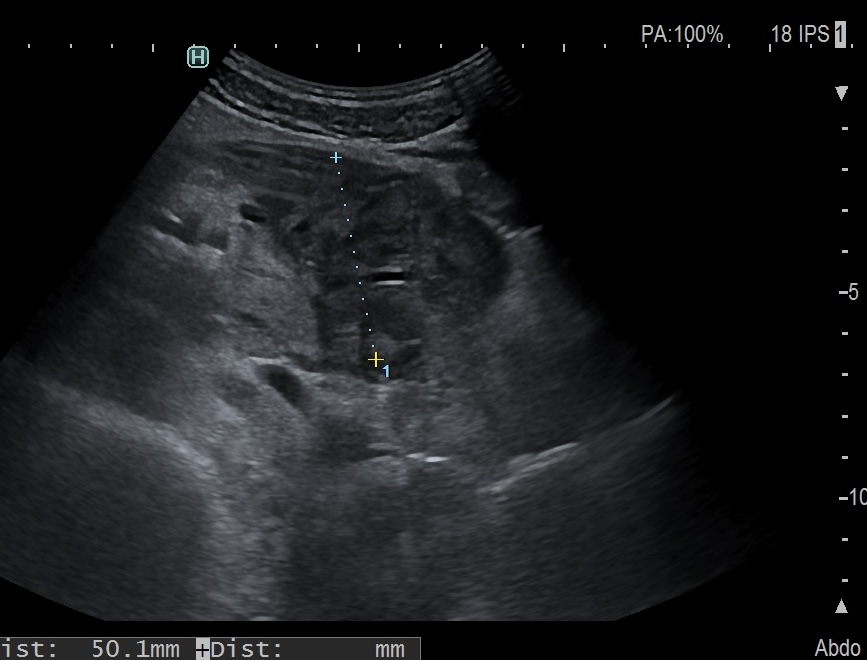

Iléïte et gros ganglions mésentériques

- En cas de colite infecteuse, on a de multiples ganglions associés à une importante infiltration du mesentère

Sigmoïde inflammé et gros ganglion (8 mm)